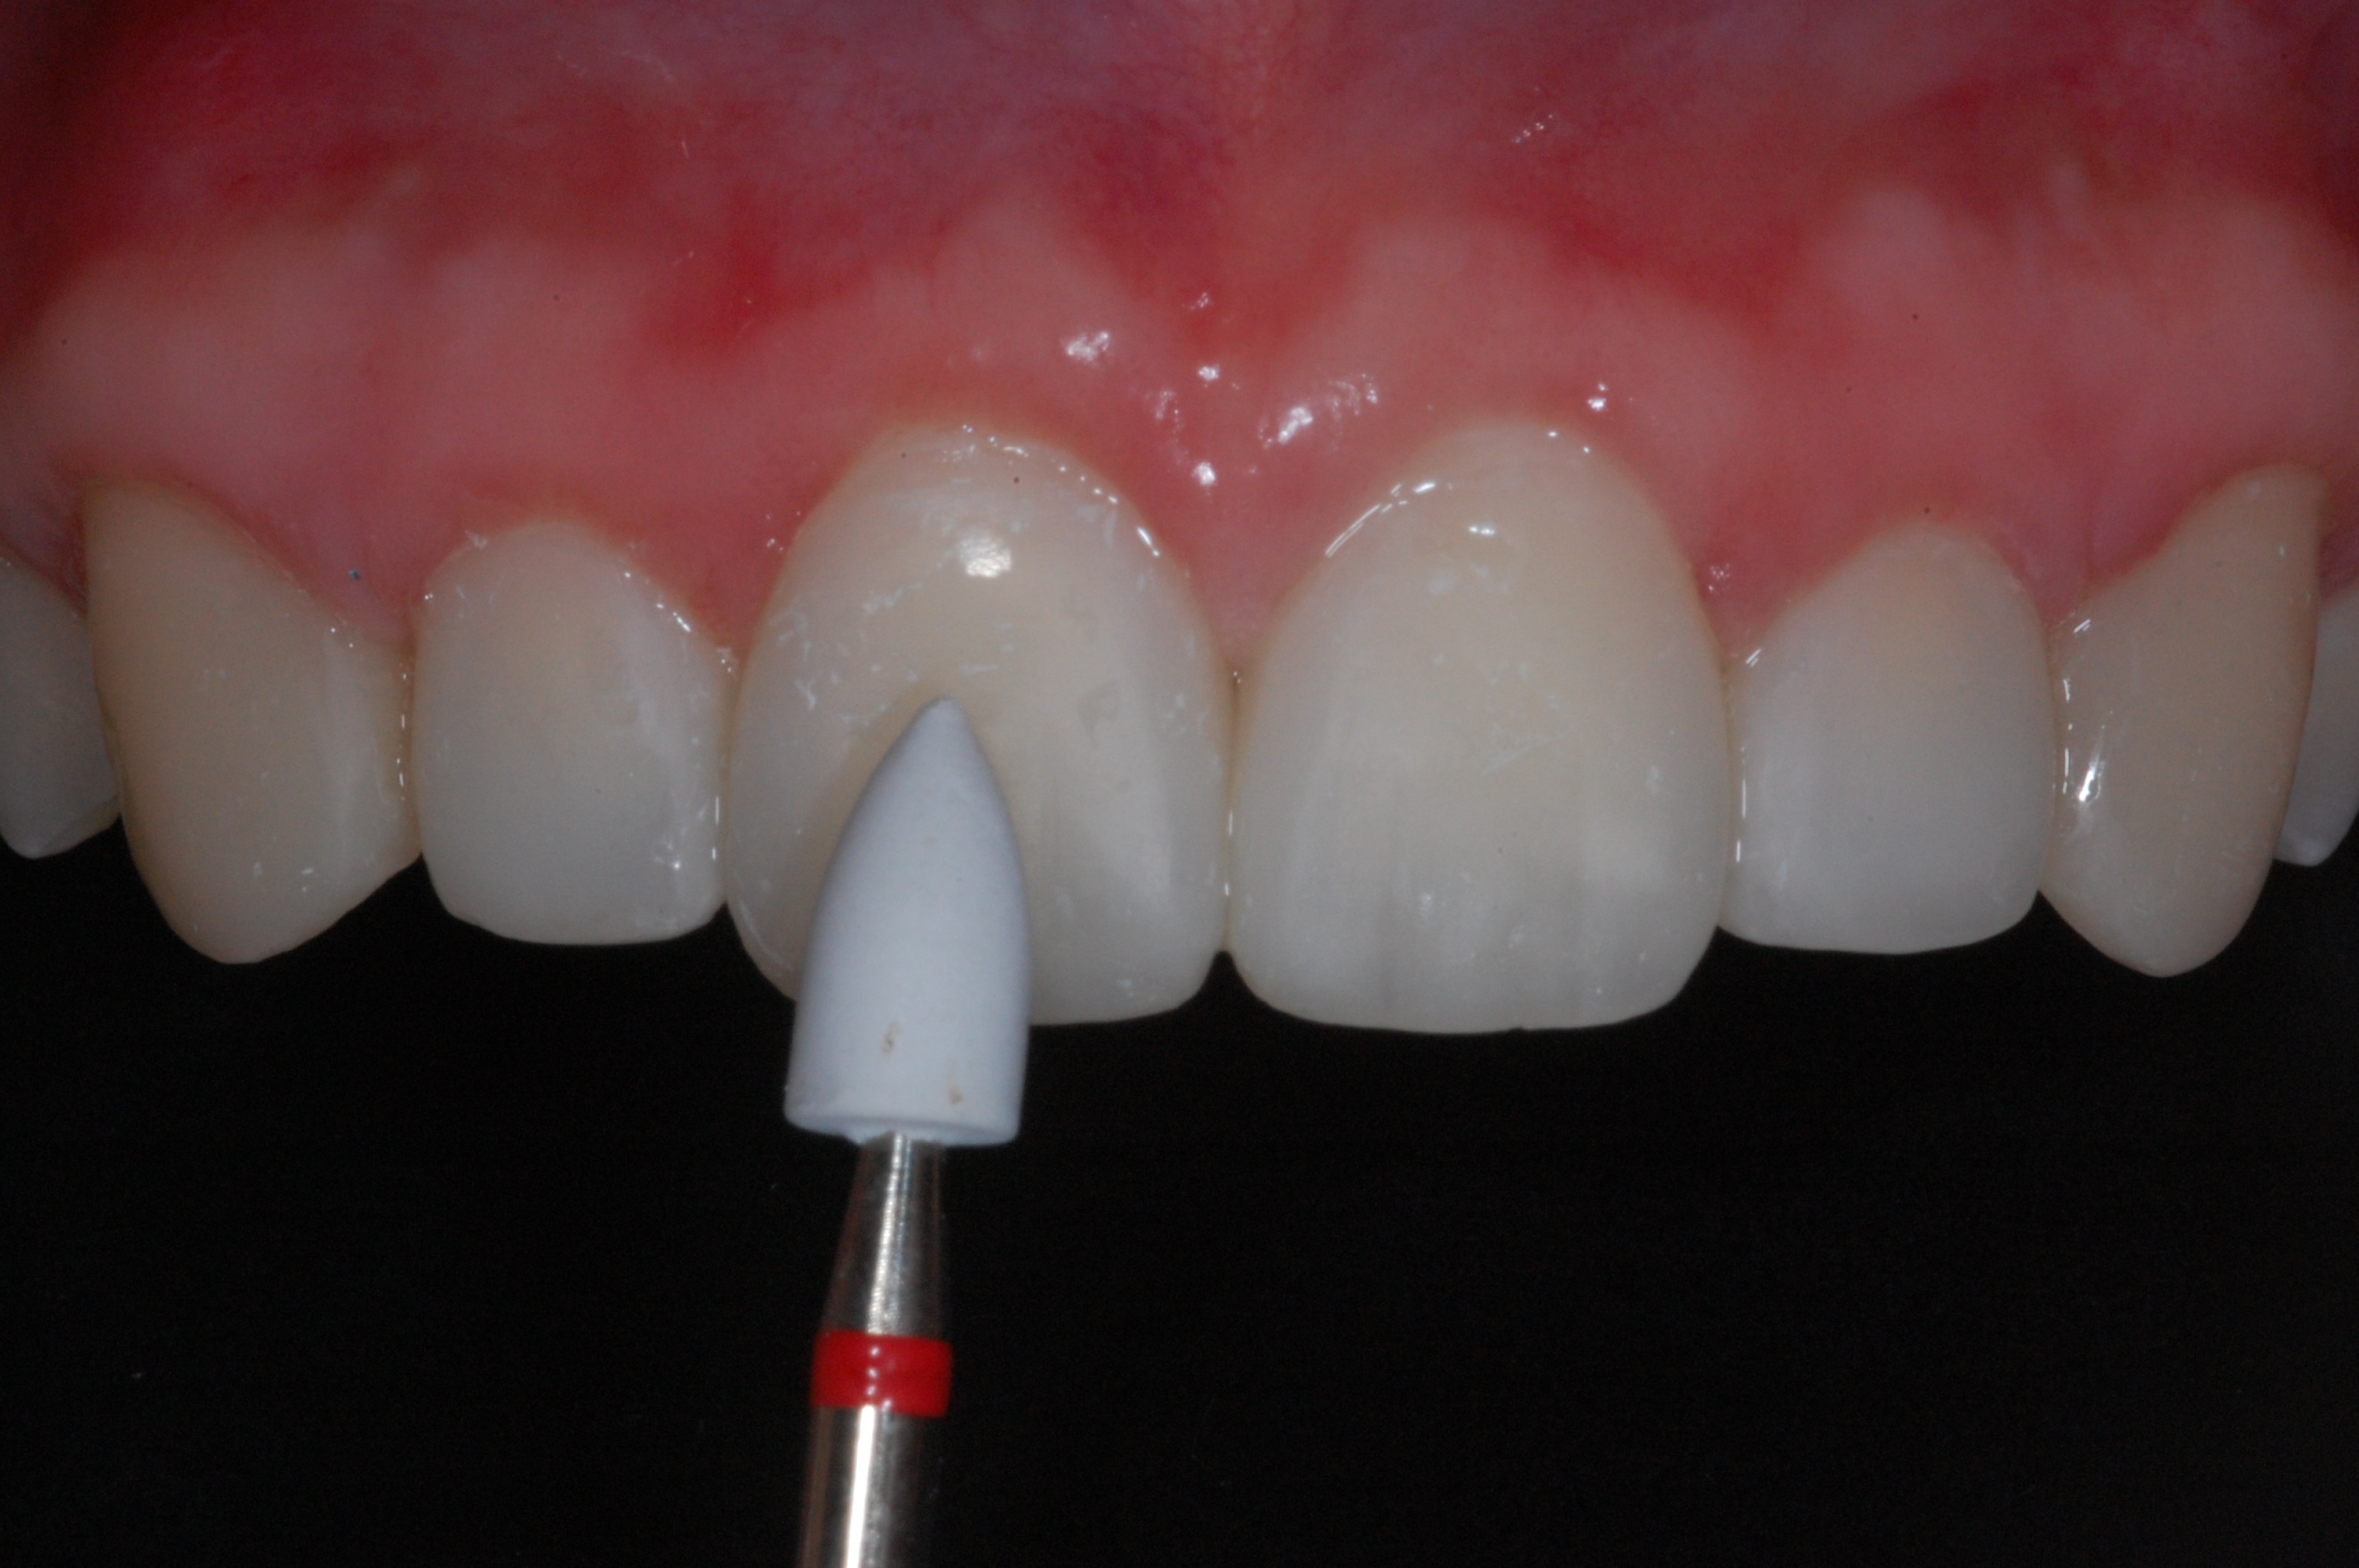

The presence of diastema, between anterior teeth, distorts a pleasing smile by concentrating the observer’s attention on the spaces. The patient’s needs and expectations must be considered in the process of treatment planning to ensure satisfaction with the treatment outcomes. There are many forms of therapy that can be used for diastema closure. A carefully developed diagnosis, which includes a determination of the causal elements and advanced treatment planning, allows the most appropriate treatment to be selected for each case. The aim of this paper is present a multidisciplinary approach as a solution to multiple diastemas in the anterior region using gingival tissue recontouring and direct adhesive restorations, with minimum wear of the dental structure, after the orthodontic intervention discussing the minimal intervention to obtain imperceptive and aesthetic final restoration. Thirty-six months after the treatment was carried out, the final aesthetic was maintained with all dental element details and gingival tissue harmony, without recurrence of periodontal pockets and the preservation of the tooth color and shape.